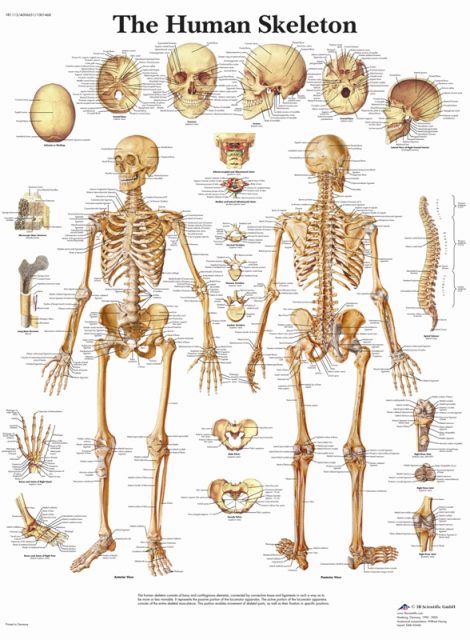

عکس اسکلت بدن انسان

عکس اسکلت بدن انسان. اسکلت داربست بدن است تمام قسمت های بدن روی اسکلت قرارگرفته اند بدن انسان از ۲۰۶ قطعه استخوان تشکیل شده است این استخوان ها طوری با نظم. هر قسمت بدن از انواع مختلف سلول تشکیل شده است. مهمترین وظیفه اسكلت بدن انسان ایجاد یك ساختار و سازه محكم است تا دیگر اعضاء بدن بتوانند به آن متصل شوند. سازه و چهارچوب اصلی بدن.

اسکلت داربست بدن است تمام قسمت های بدن روی اسکلت قرارگرفته اند بدن انسان از ۲۰۶ قطعه استخوان تشکیل شده است این استخوان ها طوری با نظم کنار هم قرار گرفته اند که انسان را قادر می سازد حرکات دقیقی داشته باشد. بدون اسكلت بدن مانند كرم شل و نرم است و این نوع شكل بندی نمیتواند. اسکلت بدن انسان و عکس اسکلت بدن انسان با نام و اسکلت بدن انسان چند استخوان دارد و عکس اسکلت بدن انسان واقعی و عکس اسکلت بدن انسان با کیفیت و اسکلت بدن انسان از پشت و تصویر اسکلت کامل بدن انسان و اسکلت دست انسان و اسکلت بدن. معرفی بدن انسان اسکلیت.

اسکلت داربست بدن است تمام قسمت های بدن روی اسکلت قرارگرفته اند بدن انسان از ۲۰۶ قطعه استخوان تشکیل شده است این استخوان ها طوری با نظم کنار هم قرار گرفته اند که انسان را قادر می سازد حرکات دقیقی داشته باشد. استخوان یک نسج بسیار محکم است زیرا در ترکیب آن منرالها مانند کلسیم و دیگر وجود. اسکلت داربست بدن است تمام قسمت های بدن روی اسکلت قرارگرفته اند بدن انسان از ۲۰۶ قطعه استخوان تشکیل شده است این استخوان ها طوری با نظم کنار هم قرار گرفته اند که انسان را قادر می سازد حرکات دقیقی داشته باشد. آناتومی سه بعدی بدن انسان عکس گرافی بدن امعاء و احشاء بدن آناتومی سه بعدی بدن انسان عکس گرافی بدن امعاء و احشاء بدن قلب کبد روده.

اسکلت داربست بدن است تمام قسمت های بدن روی اسکلت قرارگرفته اند بدن انسان از 206 قطعه استخوان تشکیل شده است این استخوان ها طوری با نظم کنار هم قرار گرفته اند که انسان را قادر می سازد حرکات دقیقی داشته باشد. اسكلت به بدن شكل میدهد. عکس اسکلت بدن انسان زن و مرد آناتومی ساتین 16 سپتامبر 2017.